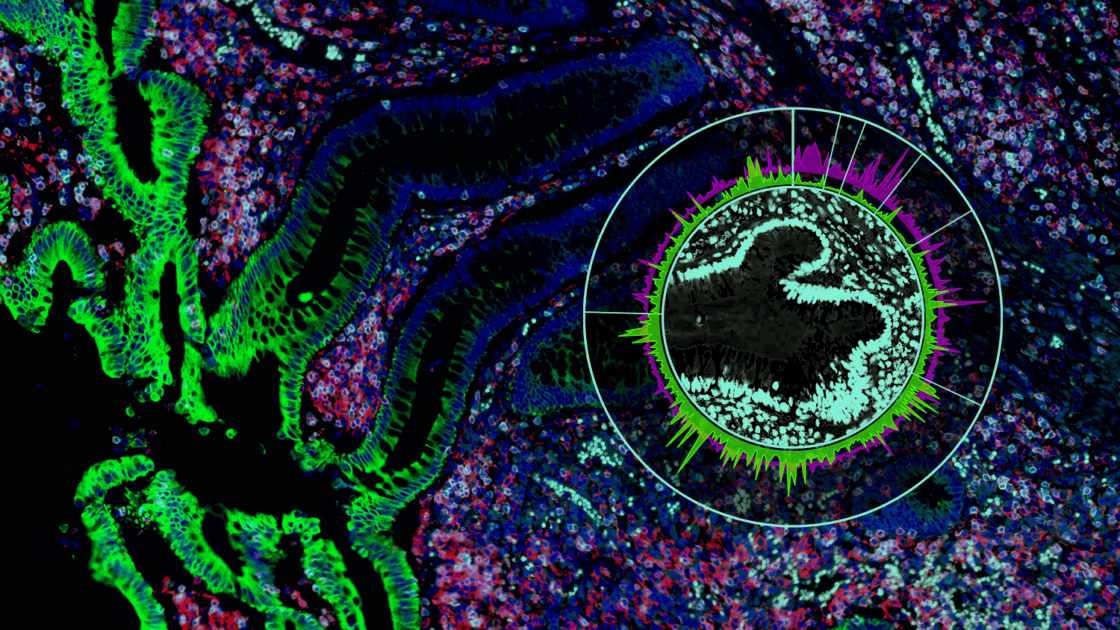

Advancing Spatial Biology Workflows through Standard Tissue Analysis Practices

The Consortium has developed best practices for scaling up GeoMx® DSP workflows for large cohort studies for biopharma and contract research organizations (CROs). Join NanoString and consortium members from Bristol-Myers Squibb (BMS), GlaxoSmithKline, and Propath as we discuss considerations for GeoMx experimental design, morphology marker selection, region of interest (ROI) selection, and data QC/analysis.